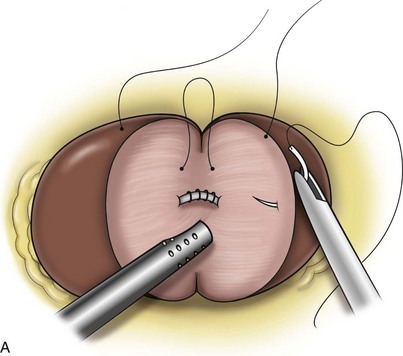

Surgical repair is performed using either a standard transperitoneal or retroperitoneal approach to fully mobilize the affected kidney and expose the fascia overlying the psoas and quadratus lumborum muscles (Chueh et al, 2002; Matsui et al, 2004) (Fig. 55–28). Beginning at the upper pole, interrupted sutures are placed to secure the lateral edge of the renal capsule to the fascia overlying the muscle (Fig. 55–29). Sutures may also be placed between the anterior renal capsule and the parietal peritoneum for additional support. Using sutures with preplaced Lapra-Ty clips (Ethicon Endosurgery, Cincinnati, OH), the initial pass is made through the fascia or peritoneum, and a second clip is placed on the suture after the pass through the kidney. An alternative technique describes the use of tension-free vaginal tape to secure the kidney (Hübner et al, 2004). By placing the needles such that the tape is passed around the lower pole of the kidney and out through the abdominal wall, the kidney is secured. Sometimes this is found in conjunction with a ureteropelvic junction obstruction that should be adressed simultaneously (Boylu et al, 2009).

Figure 55–28 The kidney is stripped of overlying Gerota fascia down to the surface of the renal capsule. All remaining attachments are divided, allowing full mobility for repositioning.

Figure 55–29 Nephropexy. Once the kidney is free of lateral and posterior attachments, multiple 2-0 sutures are placed into the capsule and the lateral edge of the fascia overlying the abdominal wall. Sutures may also be placed between the anterior renal capsule and the parietal peritoneum for additional support.